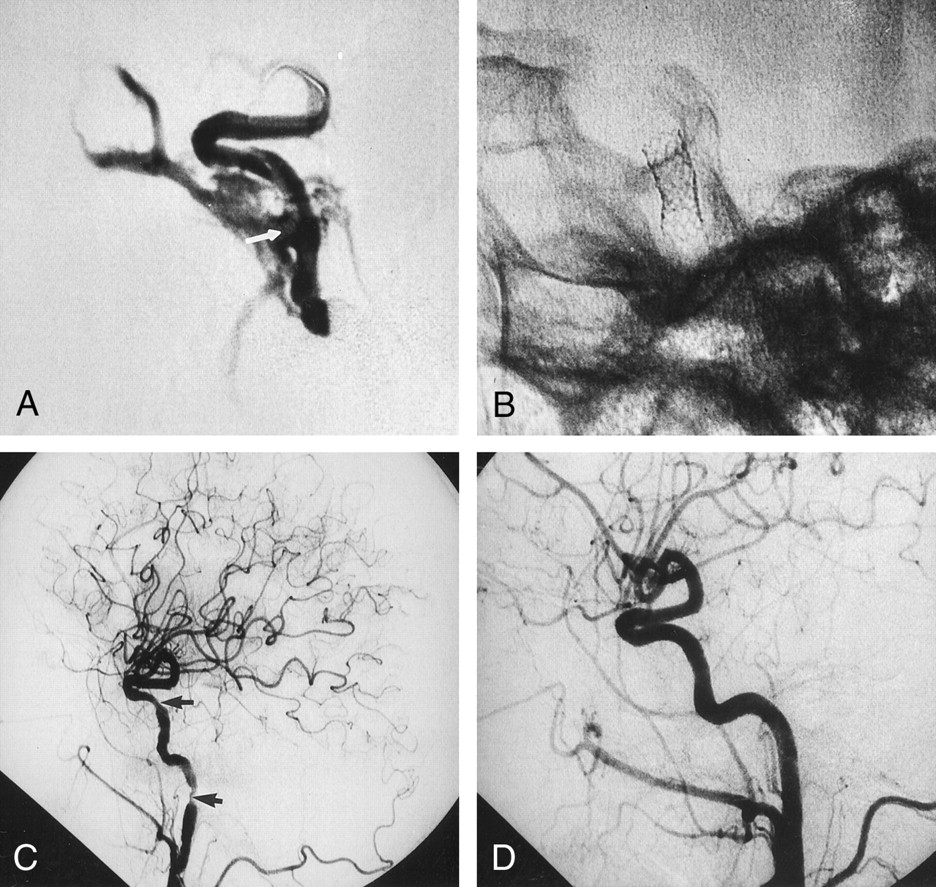

Coronary stent-graft placement to treat an iatrogenic ICA injury.

A, Contrast material injection from the guiding catheter reveals the lacerated segment of the right ICA (arrow) on this angiogram. Note that the stent-graft and microguidewire are in the ICA lumen during the injection.

B, Fluoroscopic image obtained after removal of the microballoon and microguidewire shows the expanded stent-graft in the lacerated ICA.

C, Postprocedural right CCA angiogram obtained after deployment of stent-graft reveals cessation of contrast material extravasation and closure of the CCF. Note the focal transient spasm distal to the stent-graft and at the subpetrous portion of cervical ICA (arrows).

D, Right CCA angiogram obtained 3 mo after the procedure demonstrates patency of the ICA, with no contour irregularity.

Standard cerebral angiography was performed with general anaesthesia by using a unilateral femoral approach. This examination revealed contrast material extravasation into the sphenoid sinus resulting from a laceration in the cavernous segment of the right ICA and a high-flow CCF with some retrograde cortical venous drainage (Fig 1A and B). Detachable balloon embolization was initially proposed; however, selective left ICA injection with external compression of the right common carotid artery resulted in a prominent delay (6-s delay) in the arterial, parenchymal, and venous phases in the right hemisphere (Fig 1C and D). Since the collateral circulation was not sufficient for balloon occlusion, we decided to attempt coronary stent-graft placement to treat the injury. A microcatheter (Rapid Transit-21; Cordis, Miami, FL) was passed through the injured segment of the ICA by using an angled guidewire (Terumo-16; Terumo, Tokyo, Japan). The microcatheter was then replaced with a 0.014-in exchange guidewire (Luge; Boston Scientific, Maple Grove, MN), and a Jostent coronary stent-graft (4 × 12 mm; Jomed International, Helsingborg, Sweden) was hand mounted onto a coronary angioplasty balloon (4-mm balloon diameter, 20-mm balloon length; Freeway, Jomed International). The Jostent covered stent-graft consisted of an ultrathin (75-μm) polytetrafluoroethylene graft material layered between two stents with reduced wall thickness. (The “CE” mark on this device certifies the manufacturer’s confirmation that the device satisfies both German and European safety and/or quality requirements.) The stent-graft and balloon were advanced to the injured segment of the ICA over the exchange guidewire that had been advanced into the right supraclinoid ICA (Fig 2A). The loaded balloon catheter was positioned at the level of the ICA injury. After a control angiogram was obtained, the stent-graft was inflated to 8 atm. The balloon was then deflated while negative pressure was applied, and the balloon was removed (Fig 2B). A repeat diagnostic arteriogram showed total closure of the lacerated portions of the ICA and CCF. Two spasmodic areas—one distal to the stent-graft and one at the cervical portion of the ICA—were noted (Fig 2C). These were assumed to be associated with irritation resulting from the advancement of the stent. Because spasm could have compromised the flow, 100 mg of a mixture of papaverine and isotonic sodium chloride solution was administered by means of manual injection. Upon completion of the procedure, the nasal hemorrhage ceased, and the patient was transferred to the intensive care unit. Follow-up arteriograms, obtained 3 mo after the patient was discharged, showed absent filling of the CCF, with normal patency of the ICA. The follow-up angiographic study showed no evidence of intimal hyperplasia or concomitant vessel stenosis (Fig 2D).